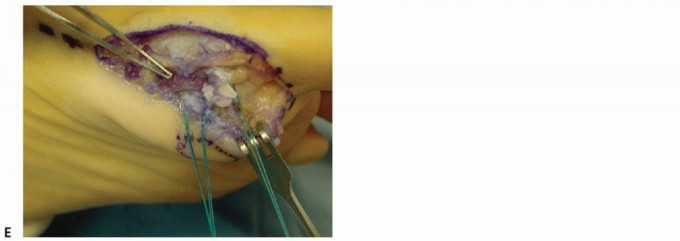

In acute cases, a rim of stout capsule typically remains on the base of the proximal phalanx. In the chronic situation, the sesamoid complex may appear redundant, often due to intervening scar tissue or elongated, weakened soft tissues at the site of injury (TECH FIG 2A). We recommend excising the redundant scar tissue sharply and advancing the proximal intact and healthy portion of the complex (TECH FIG 2B).

Distal ruptures require primary repair of remnants from lateral to medial, working around the FHL tendon (TECH FIG 2C). The hallux is held in approximately 15 degrees of plantarflexion as sutures are secured.

If the soft tissue is contracted and cannot be advanced to allow a primary repair, the FHB and abductor hallucis may be fractionally lengthened.

If soft tissues are inadequate, suture anchors or drill holes to the plantar aspect of the base of the proximal phalanx may be used (TECH FIG 2D,E). A transverse drill hole can also be created in the distal pole of the tibial sesamoid if there is an absence of soft tissue for repair on the proximal aspect.

TECH FIG 2 • A. Turf toe variant with intact but redundant plantar complex. B. Redundant tissue is transversely excised and the remaining defect is repaired primarily. C. Repair proceeding from lateral to medial and working around the intact FHL tendon. D. In the absence of healthy tissue at the base of the proximal phalanx, suture anchors can be used to advance the plantar complex. E. Radiograph showing anchors in the proximal phalanx. -